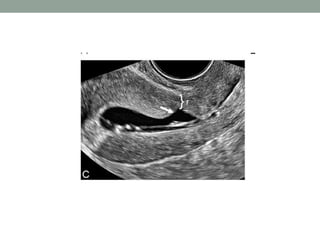

The document discusses the concept of cesarean scar niche, defining it as indentations in the myometrium that can lead to various complications such as uterine rupture and adverse reproductive effects. Factors contributing to this condition include surgical techniques and patient-related issues, with symptoms like pelvic pain and spotting. Diagnostic methods and potential treatment options, including medical therapy and surgical correction, are also highlighted.